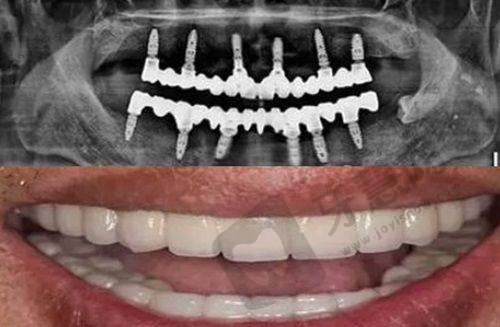

All - on - 4/6全口种植牙:通过4颗或6颗种植体支撑全口牙,减少种植体数量,缩短治疗周期,为全口缺牙患者提供效率高的解决方案。